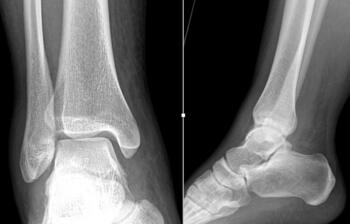

We presented the option of a patient-specific partial talar replacement with a plan to resect and replace the entire lateral shoulder. As part of the design process, the implant had custom cut guides that would sit on the talar neck, temporarily secured in place with smooth wires. This guide would then correlate with the final implants to ensure the appropriate amount of bone removal and allow more accurate bone resection. In addition, the design incorporated two stems in the final implant to add stability and fixation surface area. Three sizes of implant allowed intra-operative flexibility.

The incision was the typical anterior ankle approach. This would limit location of incisions for potential future issues or conversion to fusion or total implant. We then exposed the distal tibia and dorsal neck of the talus. Placing the prefabricated custom cut guide onto the neck of the talus, we then checked this under fluoroscopy to ensure placement, and the proper orientation and amount of lateral dome to be removed. We then pinned this guide in place with predetermined holes. A reciprocating blade limited blade excursion and minimized potential for injury to adjacent structures. After removal of the damaged piece of talus we placed the trials. The goal was to have the trial flush or even slightly recessed with regard to the adjacent cartilage. During weight bearing, the native cartilage will compress, so it is important to match the weight bearing level. If the implant is proud, then during weight bearing the cartilage will naturally compress, but the implant will not, potentially giving rise to issues with load bearing around the device.

After appropriate sizing, the guide allowed creation of holes for the final implant stems. After implant placement we performed range of motion followed by layered closure and application of a posterior splint. She was kept non-weight bearing for three weeks and once the skin healed, progressed to weight bearing as tolerated. To date, one year later, there have been no issues and she has returned to work.